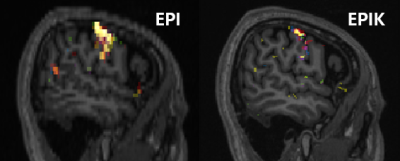

The activation regions are shown in Fig. 3. It is observed that the activated voxels from EPIK are more locally distributed around the cortical regions, whereas those from EPI are not as locally specific as EPIK. The results of EPIK further shows that the functional areas for each finger are more distinctly presented.

Figure 3. Activation regions from EPI (Left) and EPIK (Right), obtained with an uncorrected p-value of 0.001 and an extended threshold of five voxels